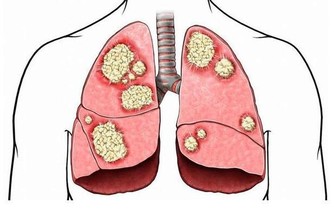

再不改掉就「屎定了」! 隨著人們對於生活享受的追求,生活中種種的設備也都越來越便利。單單是廁所就已經從以往的蹲廁發展到如今處處可見的坐廁,除了方便腳力不好的老人家上廁所以外,也可以讓其他人排便時更為舒適。只不過,這看起來很便捷的坐廁對於身體和排洩過程而言真的是理想的設計嗎? ▼如果你有便秘、腸胃炎、痔瘡、甚至是結腸癌的話,很有可能都是因為不正確的排便姿勢說造成的哦!國外資深的微生物學家-茱莉亞(Gulia Enders)指出,如果根據人體的天然構造去分析如廁的課題,大家就會發現其實蹲姿才是人類最為自然的排便姿勢。

▼因此,美國國家生物技術訊息中心(National Center for Biotechnnology Information)也鼓勵人們多採用蹲姿如廁,讓人體可以在最舒適的環境下乾淨地排出體內的廢物和有害物質,從而有效降低患上第三大常見癌症-直腸癌的機率。